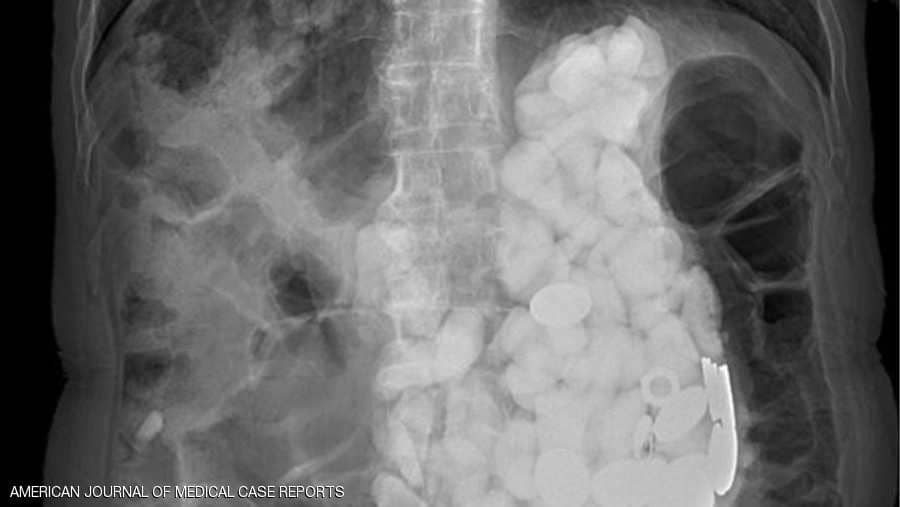

سرايا - فوجئ أطباء بعدما عثروا على مجموعة من الحجارة وأغطية زجاجات ونقود معدنية في معدة مريض، أجروا له عملية جراحية لإخراجها بعد أن تناولها أثناء تعرضه لنوبات قلق. وأدخل المريض الكوري البالغ من العمر 54 عاما إلى المستشفى، وهو يعاني آلاما حادة وانتفاخا في المعدة.

وأجرى أطباء بمستشفى Ilsan Paik بجامعة إنجي الكورية الجنوبية، مجموعة من الفحوصات لمعرفة السبب الكامن وراء هذه الأعراض، حيث شعروا بشيء يشبه الحجارة عند لمس بطنه، واكتشفوا تراكم أجسام في المعدة كلها يصل وزنها إلى كيلوغرامين.